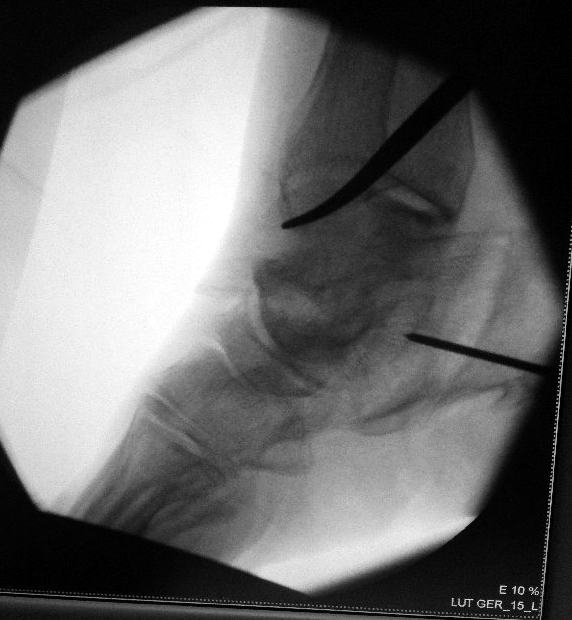

The guidewire is inserted to stabilise the cut heel bone temporarily while a screw is being inserted for final fixation.